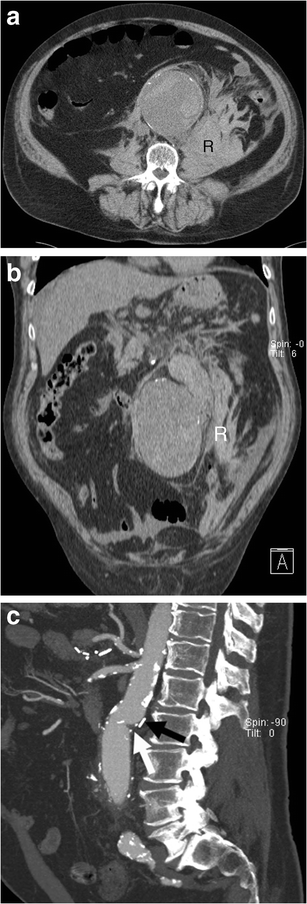

Open surgical repair. a Axial and b coronal unenhanced CT image of a 73-year-old man demonstrates ruptured AAA with a retroperitoneal haematoma (R). c Sagittal enhanced CT image of the same patient after successful open surgical repair shows the junction between the native aorta and aortic graft (white arrow) and a surgical clip (black arrow)